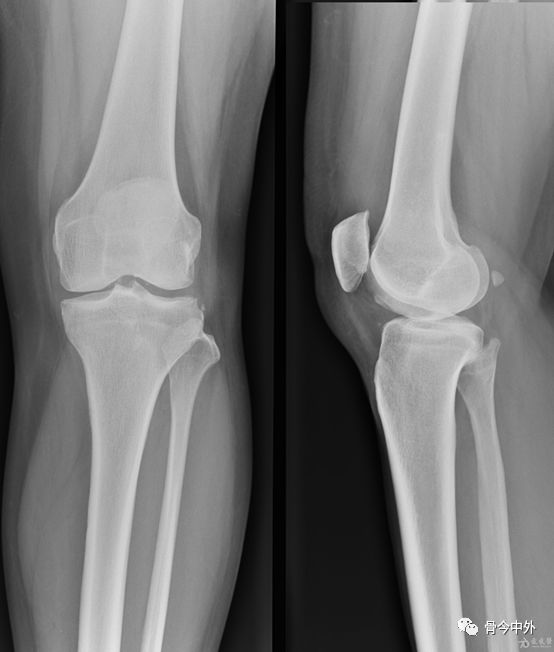

定位方法

1、以髌骨中心点,作水平线和垂直线,其第一和第二象限,各做45度的平分角,该平分线与髌骨内外缘的交点,即是进针点。

2、患者仰卧位,膝关节伸直,髌骨上缘与髌骨内外侧缘的交点为两点,斜向髌股关节中心,以45°角穿刺。

3、膝关节微屈30°左右,从髌骨下方的髌韧带内侧或外侧关节间隙垂直进针。

髌骨外上缘穿刺法

定位:髌骨外上缘处与股外侧肌交界处。按压股外侧肌下凹陷处,贴指甲刺入0.5-1cm,有落空感即可。

髌骨外下缘(外侧膝眼)穿刺法

定位:屈膝90°位,髌骨下缘、髌韧带外侧1cm处(外侧膝眼,可看到一小凹陷)。

方法:用指甲定位好后,消毒患处,针头与胫骨平台平行,向内呈45度角,穿刺进入,针头完全刺入即可。

如何选择?髌骨外下缘or髌骨外上缘

(1)对于关节内有大量积液的病人,采用髌骨外上缘进针抽液,然后顺便注射玻璃酸钠。因为关节内有大量积液的时候,积液大多在髌上囊,髌股关节间隙也比较大,髌骨外上缘进针很容易操作,也可抽出积液。而对于没有关节积液的病人,髌骨外上缘进针不太容易操作。

(2)对于没有关节积液的病人,采用髌骨外下缘(外侧膝眼)穿刺法,一定要定好位置(屈膝90度位,髌骨下缘、髌韧带外侧1cm处),采用8号针头,与胫骨平台平行,向内呈45度角,针头完全刺入,有一种落空感,有时回抽会抽出关节液,此时可放心注射;回抽如没抽出关节液,可以注射玻璃酸钠,如果注射时比较轻松,那就没有问题,如果注射时比较费力,病人感觉痛、胀,可以进一步向里面插下针头,左右移动下,注射时比较轻松病人无不适即可再注射。只要熟练操作,定位正确,及时调整,病人很少出现注射后不适的。